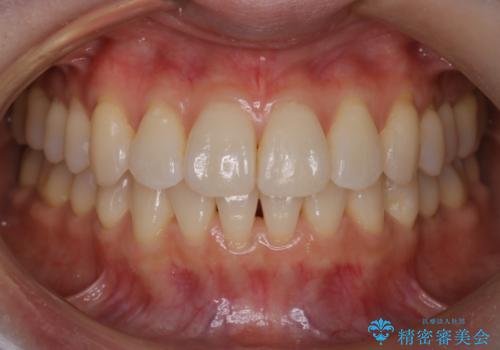

【非抜歯】インビザラインで正しい噛み合わせを

【非抜歯】インビザラインでガタつきと口元を改善!非抜歯でも印象が変わる矯正治療